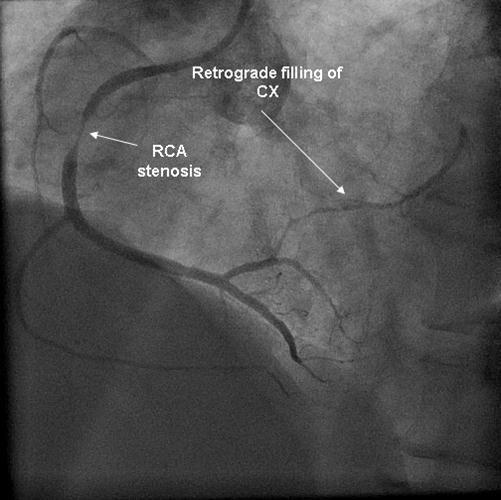

Coronary angiography was again performed. On injections into the left system, collaterals to the distal RCA were demonstrated (figure 1), arising from the left circumflex coronary artery (CX). Injections into the RCA demonstrated tight in-stent restenosis, (figure 2) and a drug eluting stent was successfully implanted. After the angioplasty, injections into the RCA were seen to retrogradely fill the CX (figure 3). The suspicion arose that maybe the left coronary artery had been inadvertently damaged during angiography, so the left coronary was again cannulated and injections performed, demonstrating entirely normal left main and CX arteries. However, the collateral flow that had previously been demonstrated from the CX to the RCA was no longer apparent. On review of the previous angiogram, it was noted that the RCA retrogradely filled the CX despite the original significant stenosis (figure 4). In essence, it became apparent that the bidirectional filling of the RCA from the CX and vice versa was in fact a direct continuity between the vessels and not collaterals, as free flow was noted from the RCA to the CX even when both arteries were completely patent.

Figure 4.Injection into the RCA in the first angiogram, with retrograde filling of CX.

There are a few interesting points about our patient's case. He demonstrated dynamic changes in the direction of coronary flow, in parallel to the development of a stenotic lesion. Firstly, in the original angiogram, there was flow from the RCA to the CX even though there was a significant stenosis. In his second angiogram, however, no such flow was demonstrated, maybe due to the longer and more critical restenosis that had developed in the stent. Secondly, at the start of both angiograms, there was flow from the CX to RCA, an appropriate finding as a collateral vessel in the presence of an obstructive lesion in the RCA. Thirdly, it seems that when both arteries are fully patent, the bidirectional flow changes to unidirectional, from the RCA to the CX.